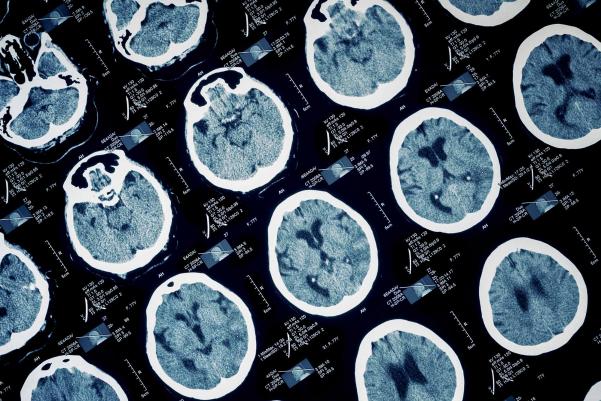

UVA Develops Imaging Approach to Help Stop Epilepsy Seizures

The new approach could help open underused surgery to patients who are currently ineligible.